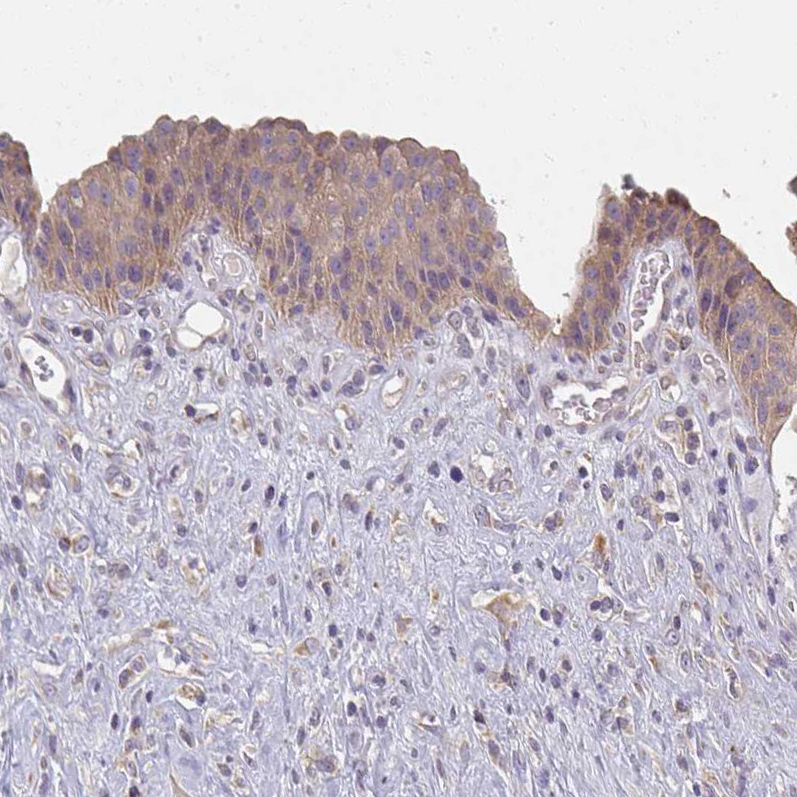

Immunohistochemical staining of human placenta shows strong cytoplasmic positivity in trophoblastic cells.